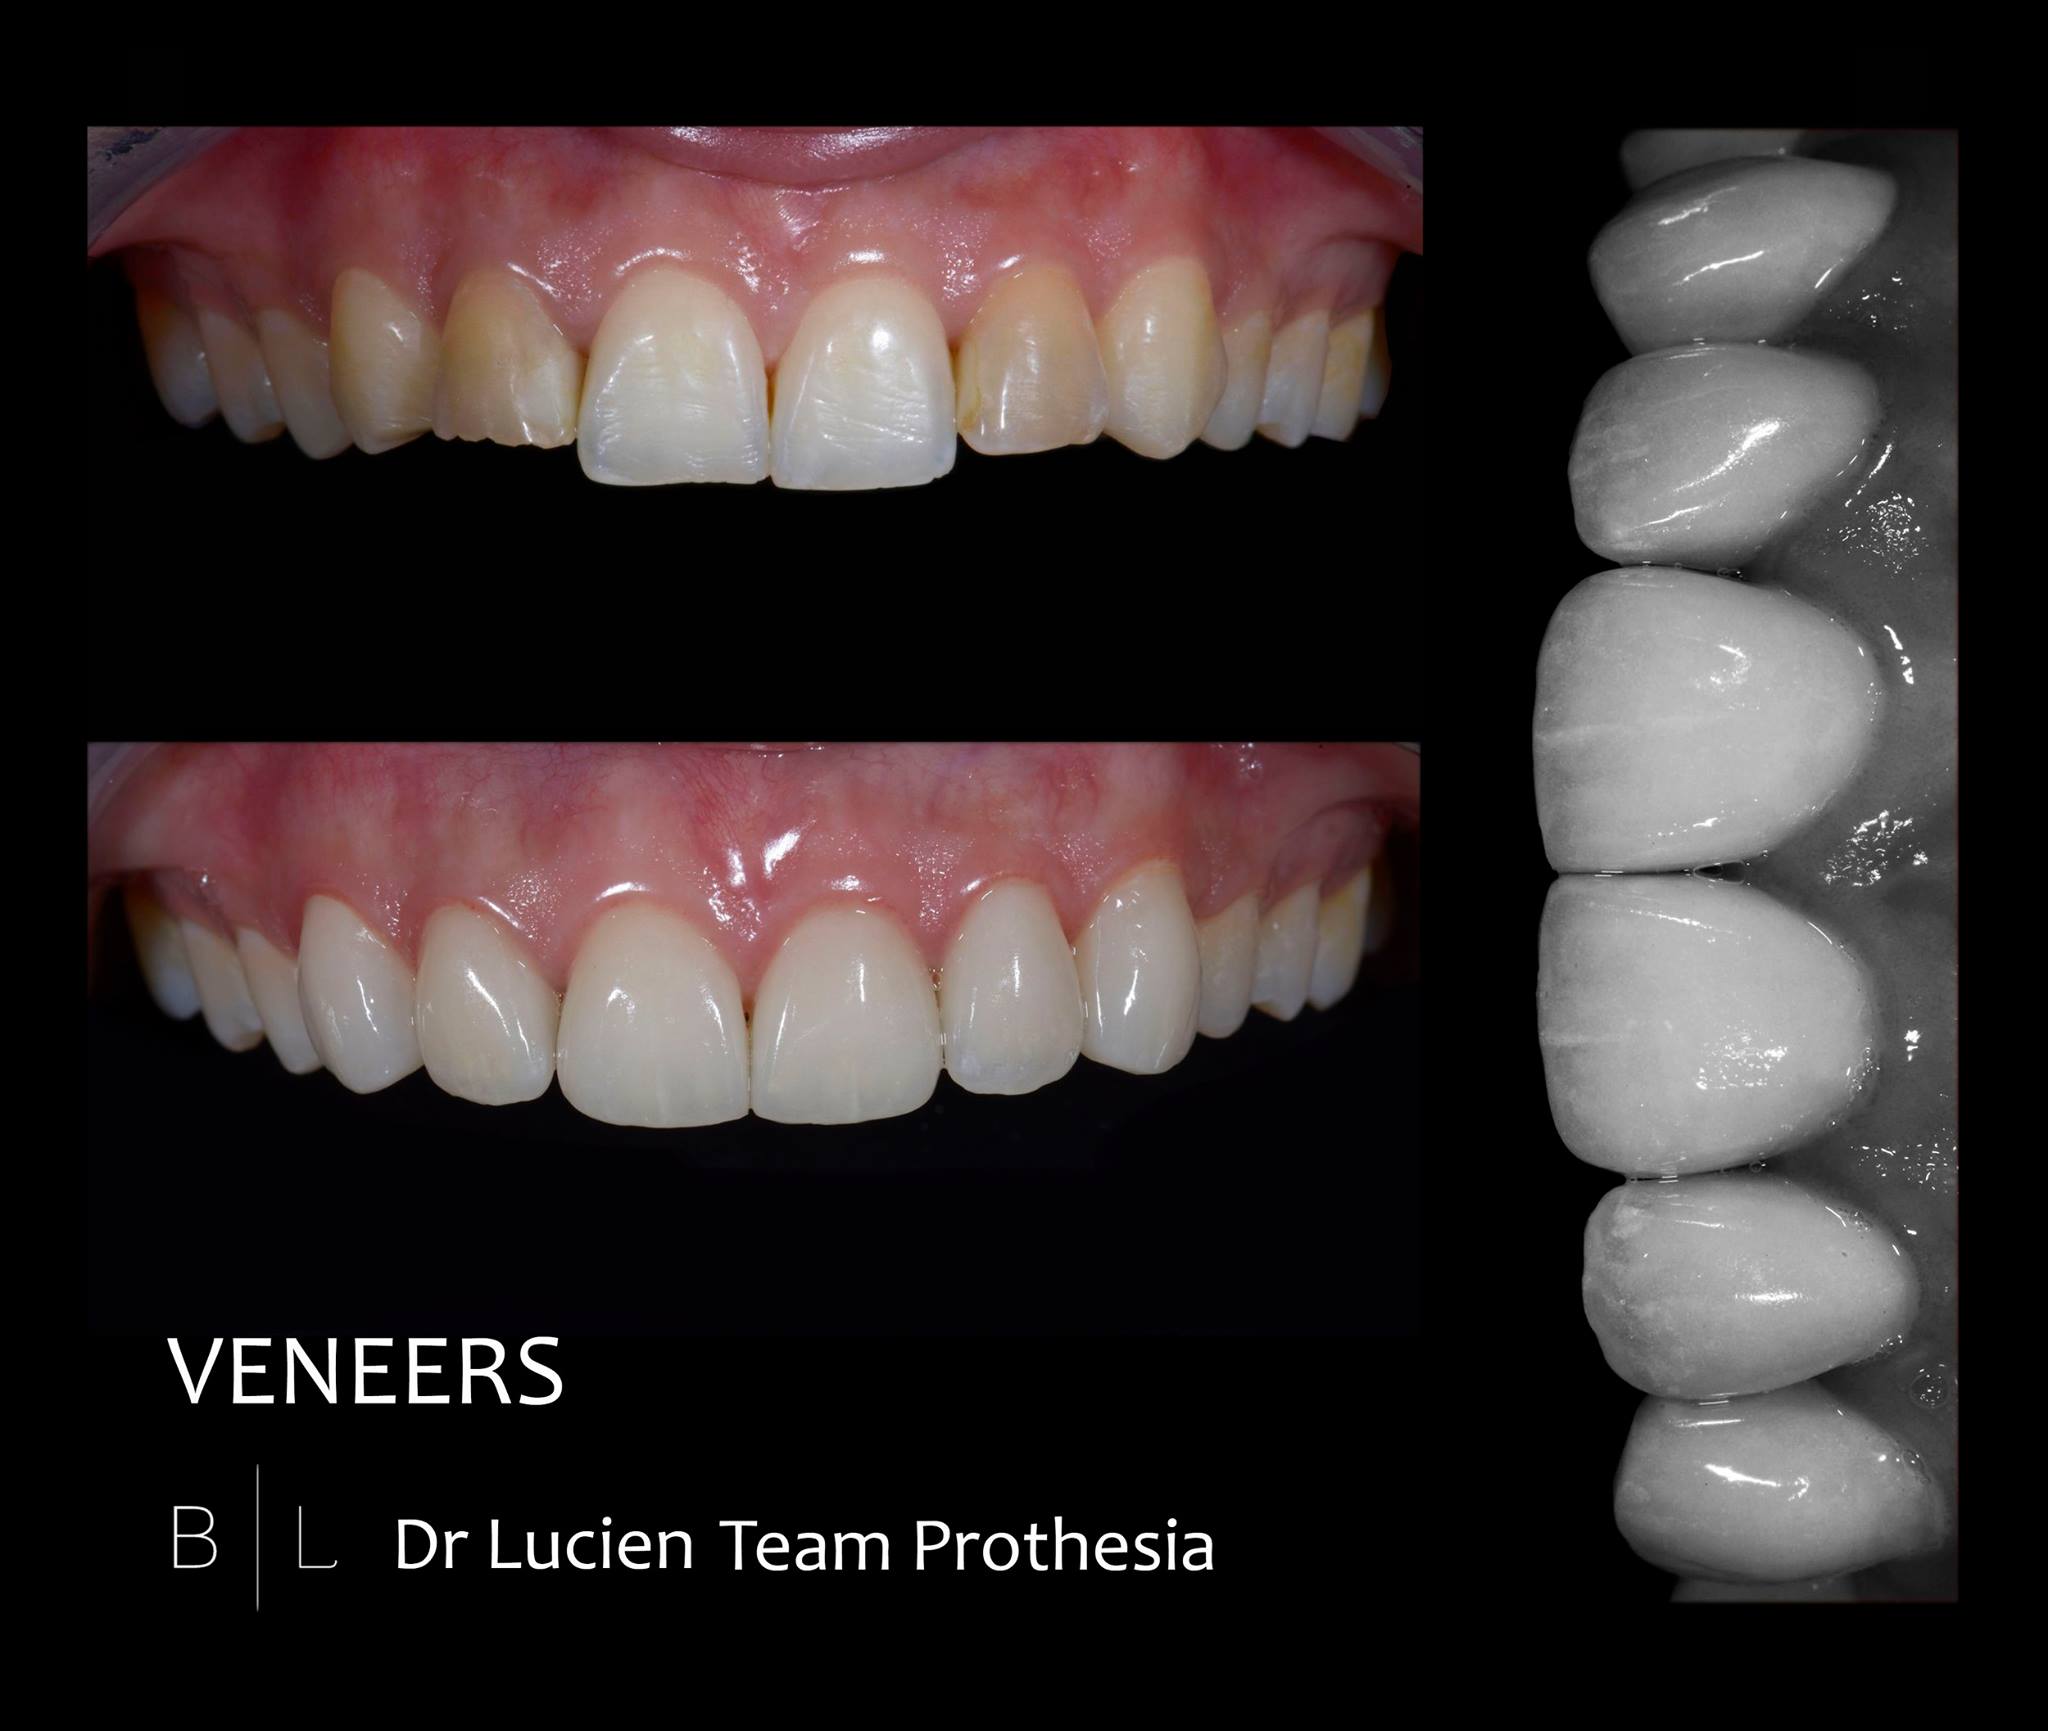

Veneers. Amazing job Team Prothesia.

Veneers. Amazing job Team Prothesia.